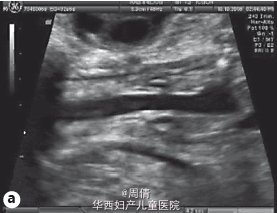

超声提示胎儿颈部冠状位正常的喉部和声带闭锁 胎儿颈部冠状位正常的喉部和声带图像 胎儿颈部冠状位正常的喉部和声带闭锁的图像